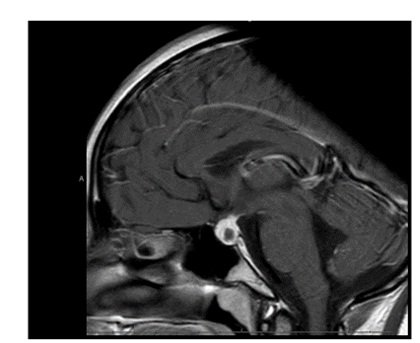

The initial pituitary MRI and contrast-enhanced MRI scan revealed the absence of the posterior pituitary bright spot and a thickened pituitary stalk with a deviation of infundibulum to the right. There was a homogenous hyperintense area within the pituitary gland with no discernable pituitary tissue. This area was hypointense on T2 (Figures 3-5). The differential diagnosis was apoplexy, hypophysitis or a proteinaceous cystic lesion replacing or compressing the pituitary gland. The optic nerves and the chiasm appeared normal. Her investigations confirmed her to have hypopituitarism with Diabetes insipidus (Table 2). Her lumbar puncture showed no CSF abnormality. Her tumor markers and Quantiferon for tuberculosis were negative. The case was discussed in multidisciplinary meeting (MDT) and with empirical diagnosis of hypophysitis, she was started on prednisolone with the replacement of deficient hormones, including Desmopressin. She showed no improvement in her clinical symptoms. A 3 month interval scan showed an increase in the size of the pituitary gland with further thickening of the stalk and optic chiasm displaced superiorly. After the second discussion in MDT, she had a pituitary biopsy. During surgery, soft yellow-white pus-like material was drained after dural incision. The microscopy showed necrotic material with a little amount of compressed anterior pituitary gland, chronic inflammation, and no evidence of adenoma or granuloma or giant cells was found. No acid-fast bacilli or organisms were seen on gram staining, and the culture for TB was negative. There was scanty growth of Propionibacterium acneformis. Her interval scan 3 months later showed complete resolution of the non-enhancing T1 hypertense pituitary tissue with a further decrease in the size of the pituitary gland. She remains on full hormones replacement. She had an insulin tolerance test that confirmed her growth hormone deficiency, and she is now on growth hormone replacement. She remains on hydrocortisone, Thyroxine, female hormone replacement, and Desmopressin.

Figure 3: MRI at presentation.

MRI is the imaging of choice for the pituitary lesions. PA can present as a suprasellar mass (65%) or as an intrasellar mass (35%). A typical PA appears as a single cystic or partially cystic mass that is hypointense on T1-weighted image and hyperintense in T2-weighted image. It can show a rim of enhancement after contrast gadolinium. The posterior pituitary bright spot is mostly absent in majority of the cases (Wang et al.). The lesion’s signal depends on protein, water, lipid content, and whether there is hemorrhage. Imaging can also show the invasion of an adjacent anatomical structure, peripheral meningeal enhancement, thickening of the pituitary stalk, and paranasal sinus enhancement [6].